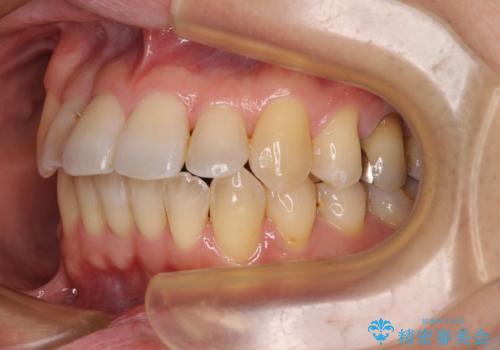

舌の突出癖の影響か、下顎前歯がなかなか整わず、治療期間は予定よりも長期間となりました。

舌突出癖改善のトレーニングの重要性を認識することとなりました。